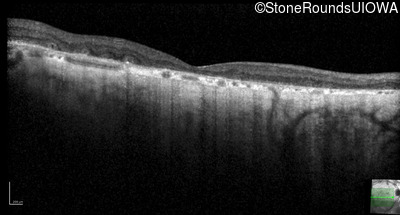

Optical Coherence Tomography - Right - 20/25 -2

Exemplar / OCT Stack